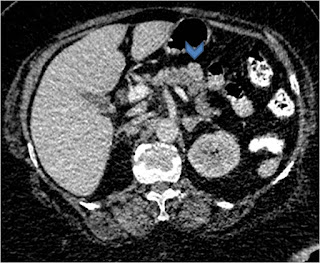

Once a diagnosis of insulinoma has been made the next most important is to localize the tumor within the pancreas for surgical planning. Owing to hyper-vascular nature, on contrast enhanced CT scan (Figure 1), insulinoma typically appear as hyperattenuating nodule with clear margins and avid enhancement in comparison to normal pancreatic parenchyma on post-contrast arterial or pancreatic phase images 2.

Figure 1. Abdominal contrast enhanced computed tomography scan (Arrow head pointing towards insulinoma)